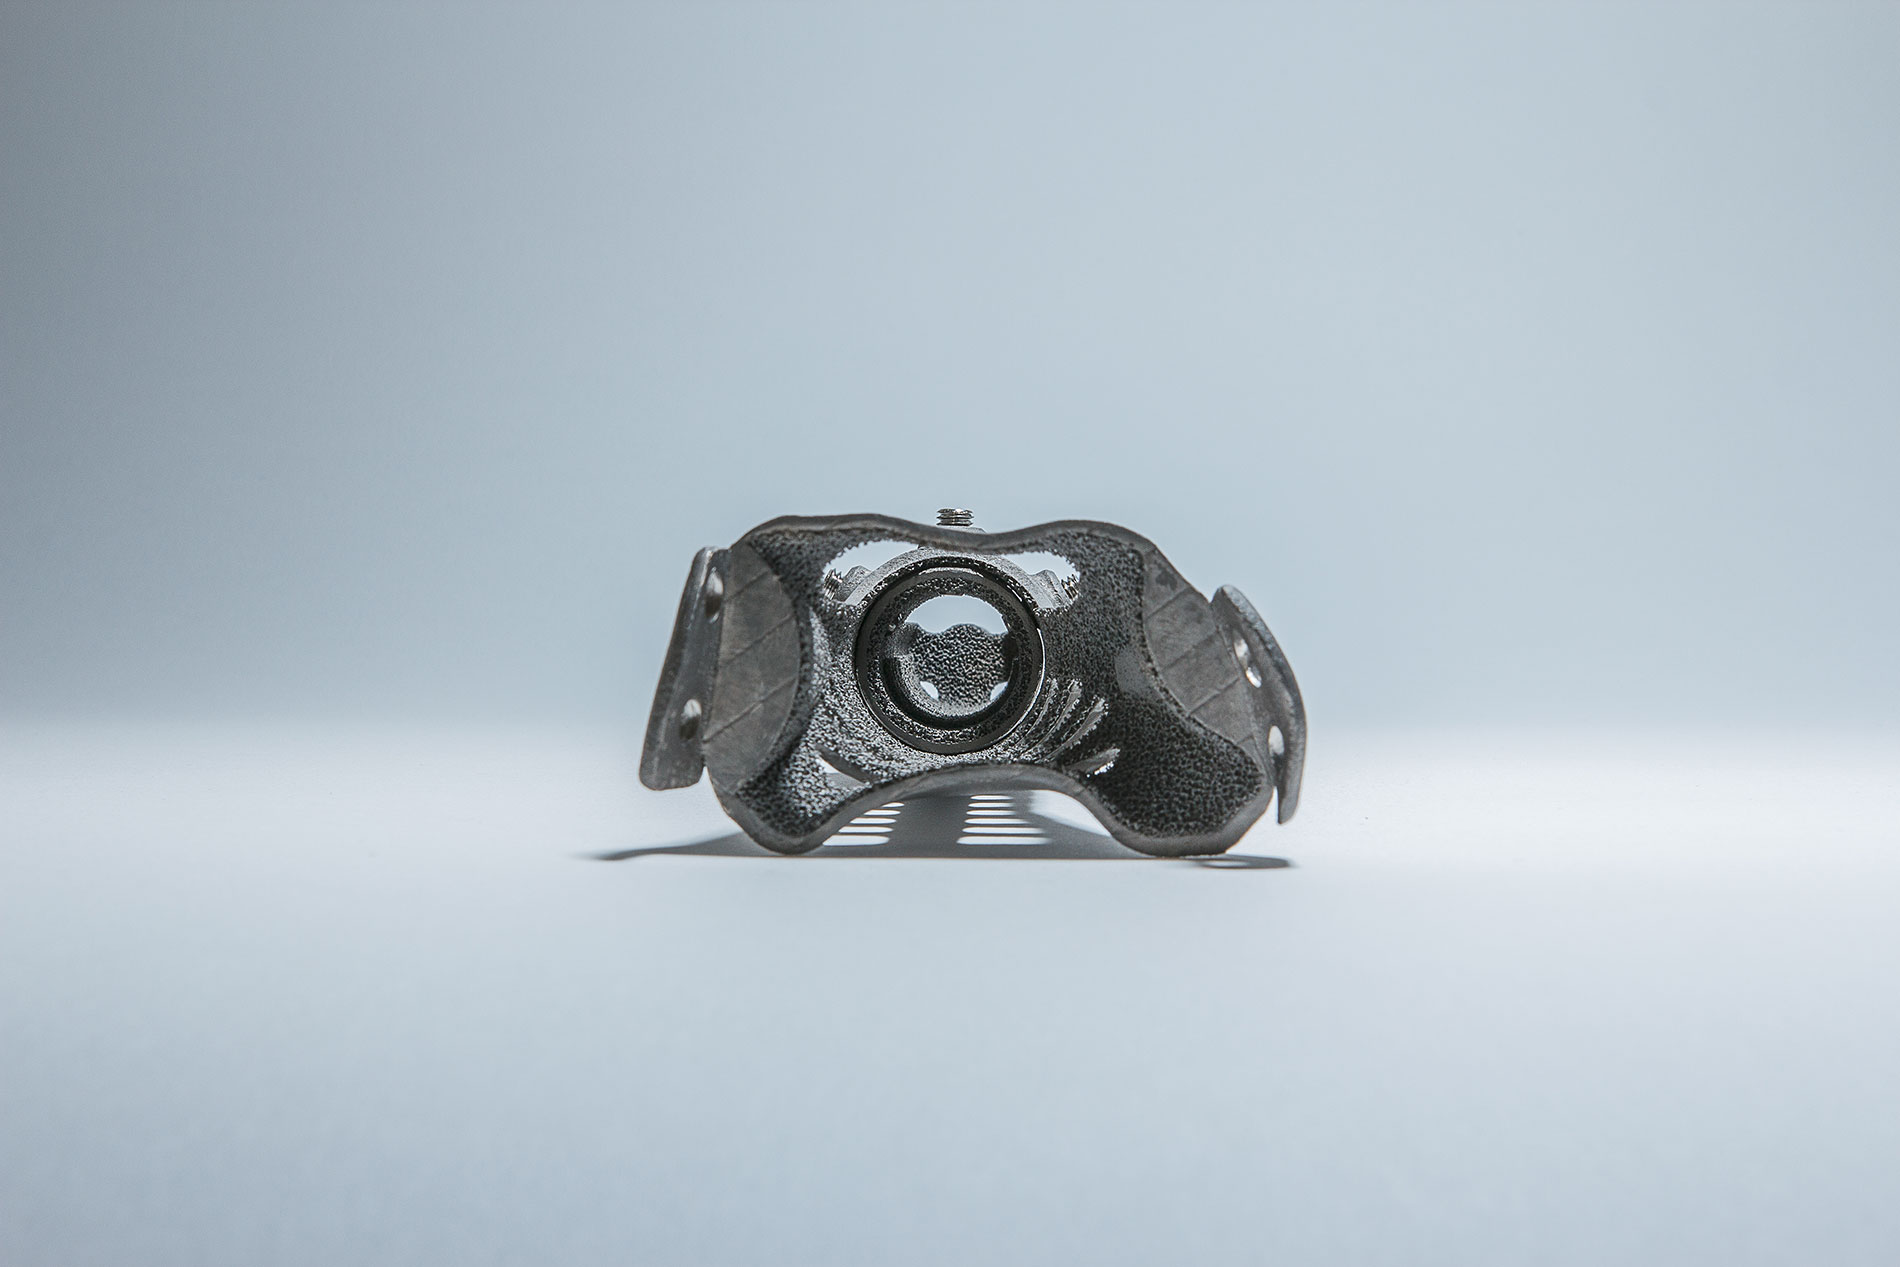

Reproducimos en nuestros implantes de titanio biocompatible la misma trama de cavidades que poseen los huesos del cuerpo humano haciéndolos livianos y extremadamente resistentes

Implantes a medida, impresos en 3D con tecnología TST® (Titanio Trabecular)

6 | Se aplica a diferentes regiones anatómicas: cráneo, ATM pelvis, etc.